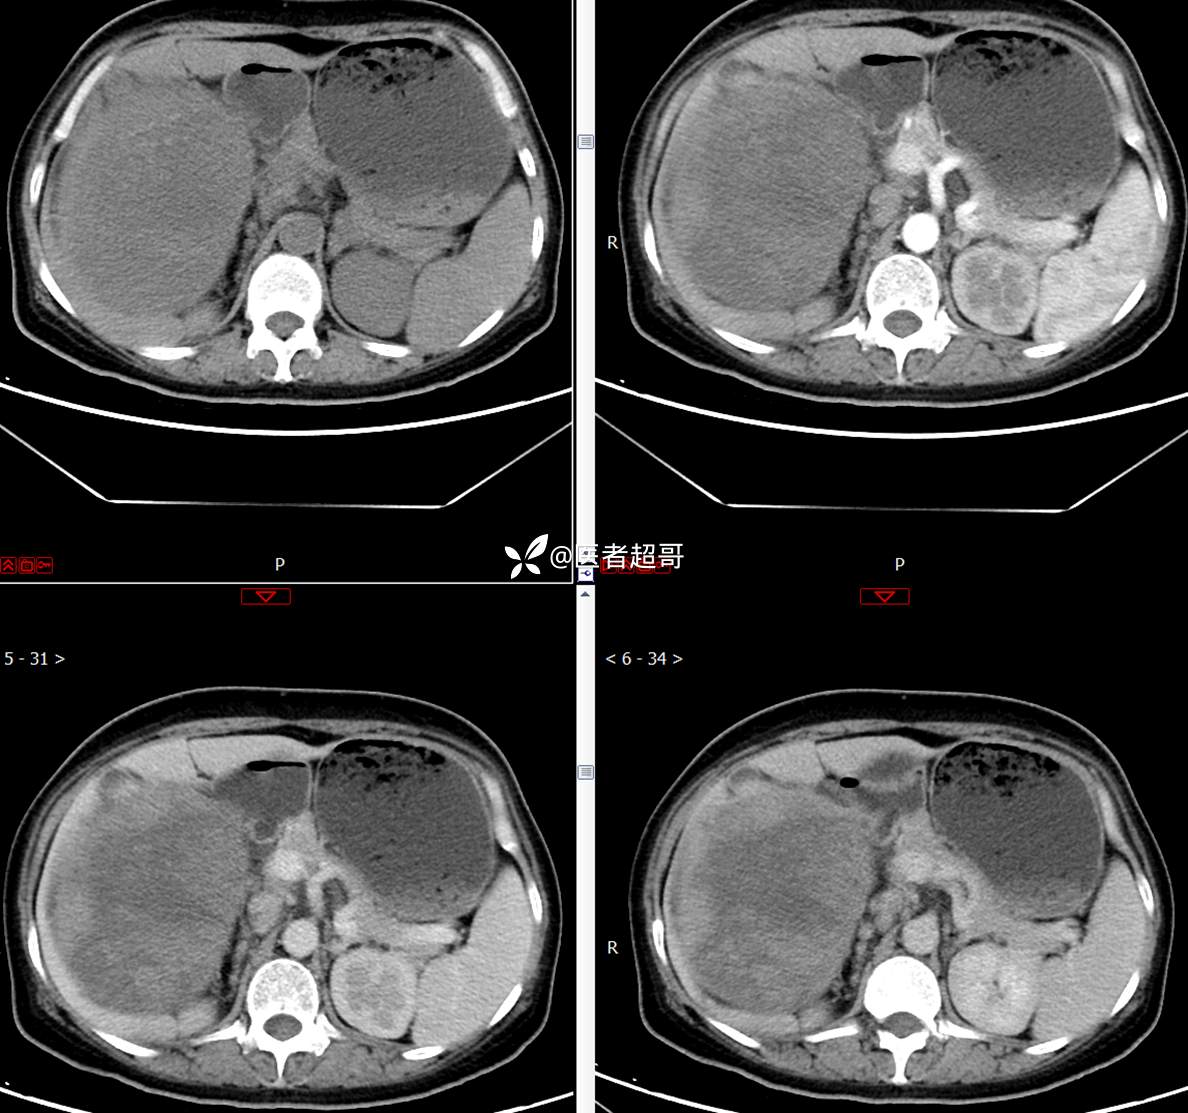

现病史:患者1周余前发现右上腹有一半球形巨大肿物,约18cm*15cm大小,既往贫血病史3年余,诉乏力,易疲劳,偶有头晕,活动后心悸,无腹痛、腹胀,无恶心、呕吐,无尿频、尿急、尿痛,无排尿困难,患者为求进一步治疗,来我院消化内科就诊,门诊行肝.胆.胰.脾.肾彩超示:右肾上部囊实性占位,范围约18.0cm×11.7cm×16.4cm,边界清,形态规则,建议进一步检查,腹膜后实性结节。我科遂以“肾肿物”收治入院,患者自发病以来,神志清、精神可,睡眠、饮食可,二便正常,体重、体力略有下降。